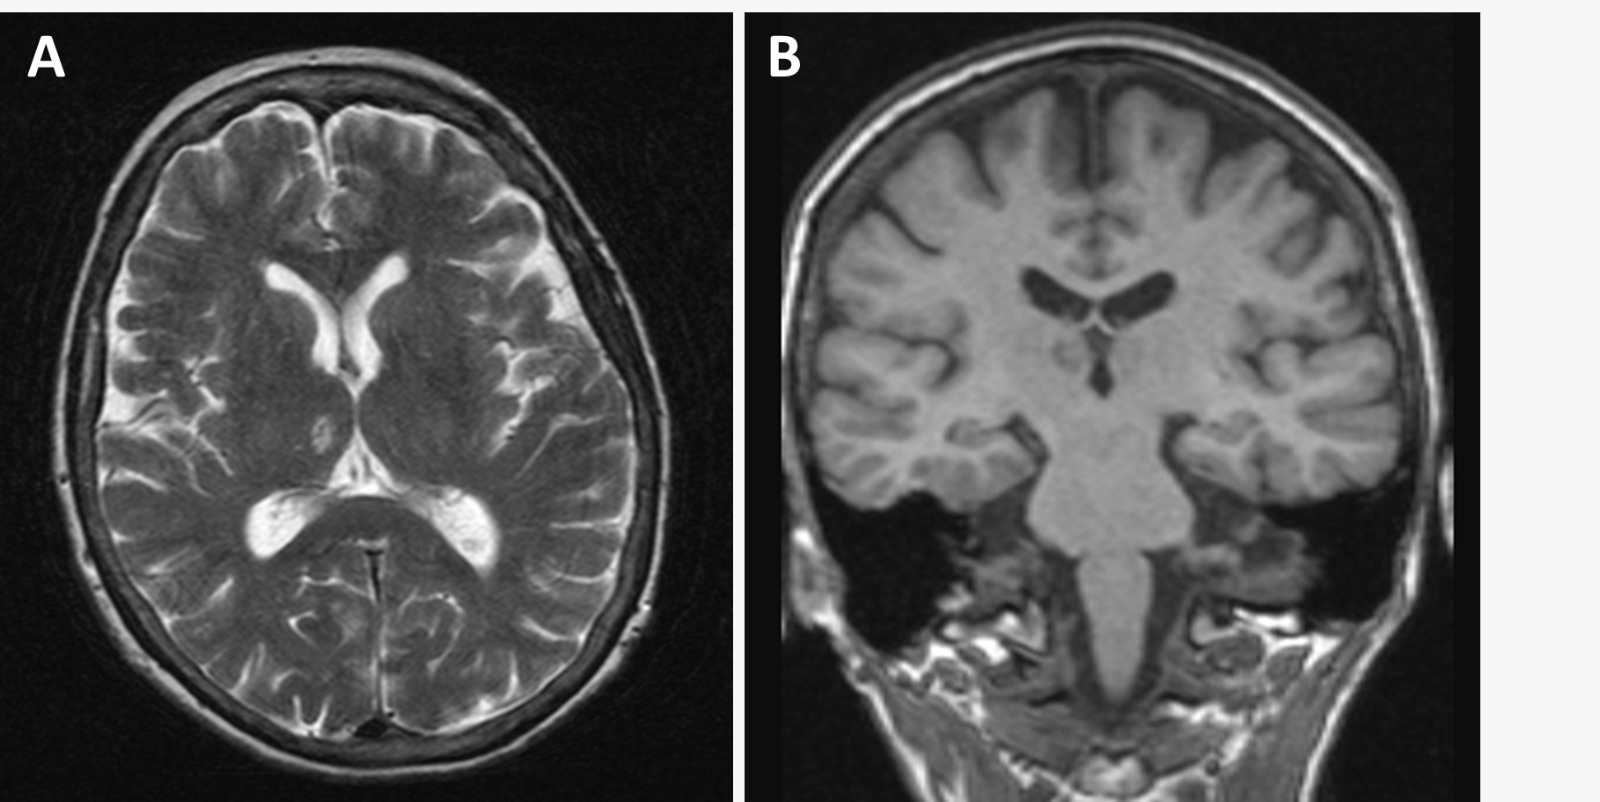

Laboratory workup showed no significant abnormalities, with negative toxicology screening. Brain computerized tomography scan revealed a subacute ischemic lesion in the right c, later confirmed by magnetic resonance imaging (Figure 1A-B). Blood and cerebrospinal fluid (CSF) tests were normal, including polymerase chain reaction and serology for central nervous system infections, neurological autoimmunity and CSF biomarkers (amyloid beta protein, total, and phosphorylated tau). Carotid and vertebral Doppler ultrasonography excluded unstable atherosclerotic plaques and clinically significant vascular stenosis, while a twenty-four-hour Holter monitor study excluded atrial fibrillation. Electroencephalography (Figure 1C) indicated mild diffuse cerebral dysfunction with more significant functional repercussion in the frontal lobes.

Figure 1A-B

Figure 1A-B.T2 (A) and T1 (B) weighted magnetic resonance imaging scan (MRI) of the brain performed 4 weeks after the onset of symptoms, showing a right thalamic oval lesion with 10 mm in diameter. There was mild symmetric posterior cortical atrophy (grade I on the Koedam scale) without mesial temporal atrophy.